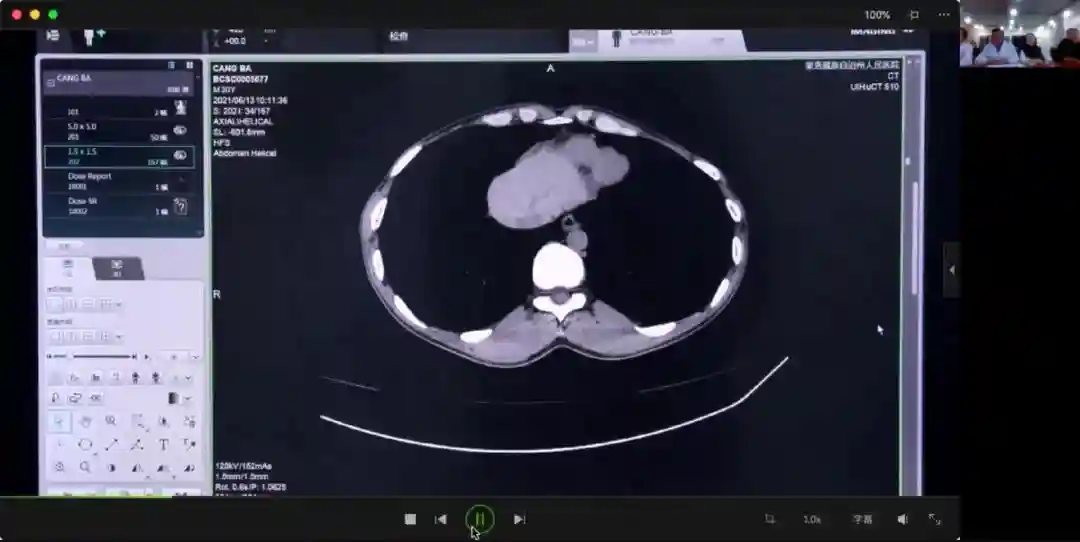

2021年6月13日

助力肝包虫病手术动态清零,董家鸿院士远程会诊青海果洛三个典型病例。“目前,青海省的肝包虫病正在进行手术动态清零,未来的工作应该投入到早期预防、早诊早治、科普宣传,建立完善的肝包虫病防控体系上。”董家鸿说道。